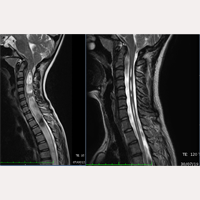

김염황. 신경-두개골-척추 증후군. 종사 질병. 소뇌 편도 밀착. 척수 내 낭포. 척추 만곡. L5-S1 좌측 추간판 헤르니아. C5-C6 추간판 돌출. 더 보기 » 26/11/2021